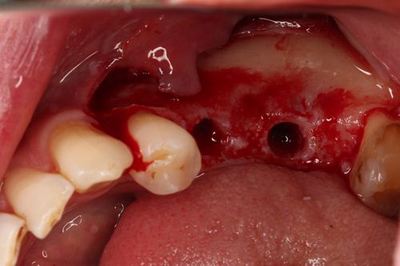

この時点で粘膜剥離します。

ドリルステップを進め最終サイズまで形成を終えました。

深度ゲージで深さと角度の確認をします。

無事埋入を終えました。

インプラント挿入ジグを外しました。

封鎖スクリューを締結し、インプラントフィクスチャーを保護します。